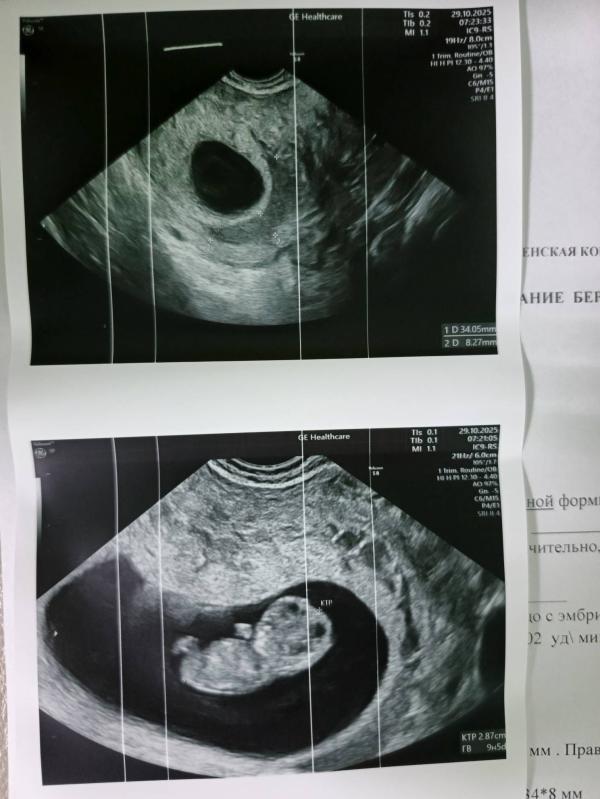

Сходила сегодня на очередное узи, опять увидели гематому, хотя на прошлом узи не было, назначили свечи . Сердцебиение 202 уд/мин, сказали в норме, но в интернете пишут на моем сроке до 177, ладно, поглядим дальше. Записали на первый скрининг на 12 ноября 😊

В 5 недель смотрели была, в 7 смотрели не было, теперь опять есть ничего не понимаю 🤷♀️